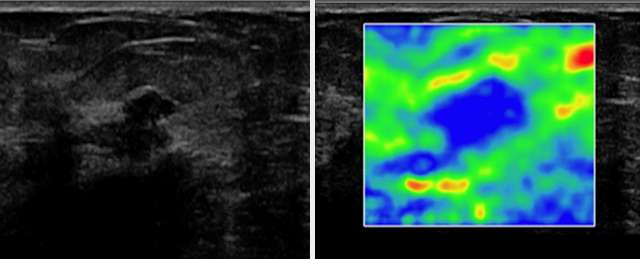

Another useful tool in conjunction with Doppler sonography is ultrasound elastography (sono-elastography), which uses sound waves to assess the mechanical properties of tissues (firmness). Soft lesions “deform” from sound waves more so than firm lesions. In general, malignant lesions tend to be firmer (deform less) than benign lesions. One application of this property is with Strain Elastography, where a color scale can be used to give a qualitative analysis of the firmness of a lesion. The two figures below, courtesy of the article “The Role of Sonoelastography in Breast Lesions” (Richard Barr, et. al), give an example of Strain elastography in evaluating a hypoechoic breast mass with irregular borders in a 63-year-old woman (left image). On elastography (right image), blue represents stiffer breast tissue and red, softer tissue. This lesion is blue, indicating a firm lesion, correctly increasing suspicion, as this lesion was biopsied and proven to be invasive ductal carcinoma.